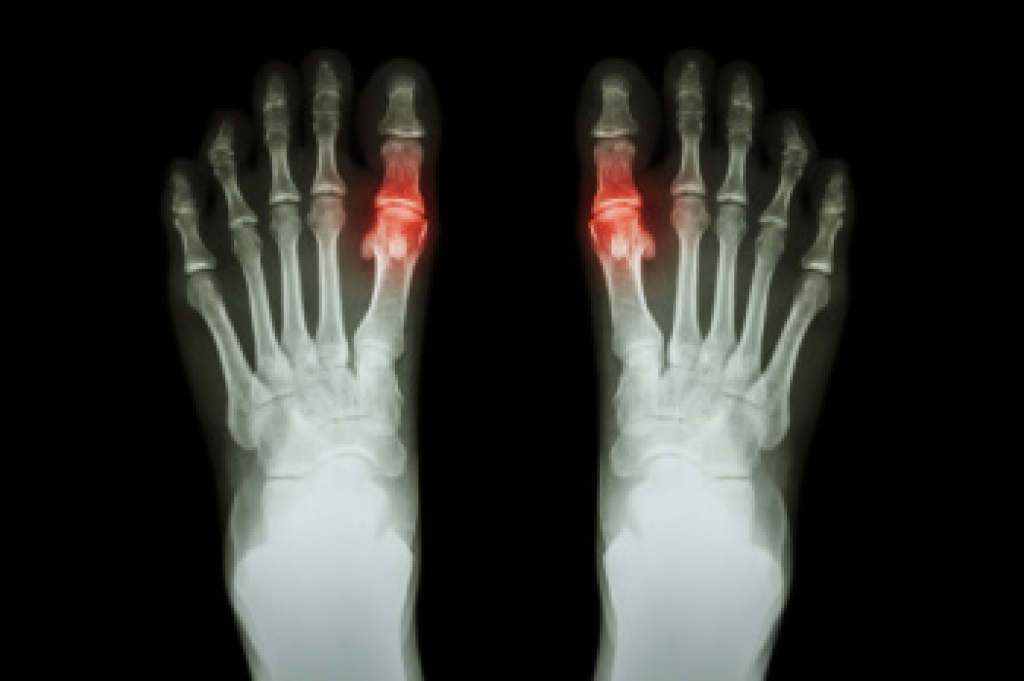

Chronic tophaceous gout is an advanced form of gout that develops when uric acid builds up in the body. The result is hard deposits, called tophi, that form around joints and soft tissues. Uric acid is a natural waste product, but high levels can lead to crystal formation that triggers inflammation, causing swelling, warmth, and severe pain. Over time, these deposits may grow and cause joint damage, stiffness, and reduced movement. They can also press on nearby nerves and affect walking. A podiatrist can diagnose chronic tophaceous gout through imaging or fluid testing, which identifies uric acid crystals. Treatment options include medication to lower uric acid levels and reduce inflammation, as well as care to protect the joints and prevent further damage. In severe cases, surgery may be needed to remove large tophi. If you are experiencing severe pain from gout, it is suggested that you make an appointment with a podiatrist for treatment.

Gout is a form of arthritis that is characterized by sudden, severe attacks of pain, redness, and tenderness in the joints. The condition usually affects the joint at the base of the big toe. A gout attack can occur at any random time, such as the middle of the night while you are asleep.

- Inflammation and Redness -Affected joints may become swollen, tender, warm and red